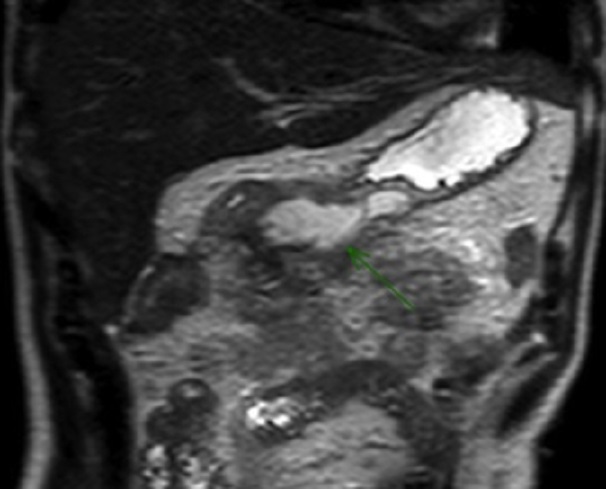

Image radiologique IRM d'une

transection a distal du corp pancreas avec aspect de

epanchement peri-pancreatique se retrouve sur cette

coupe . Coupe coronal IRM de l'abdomen |